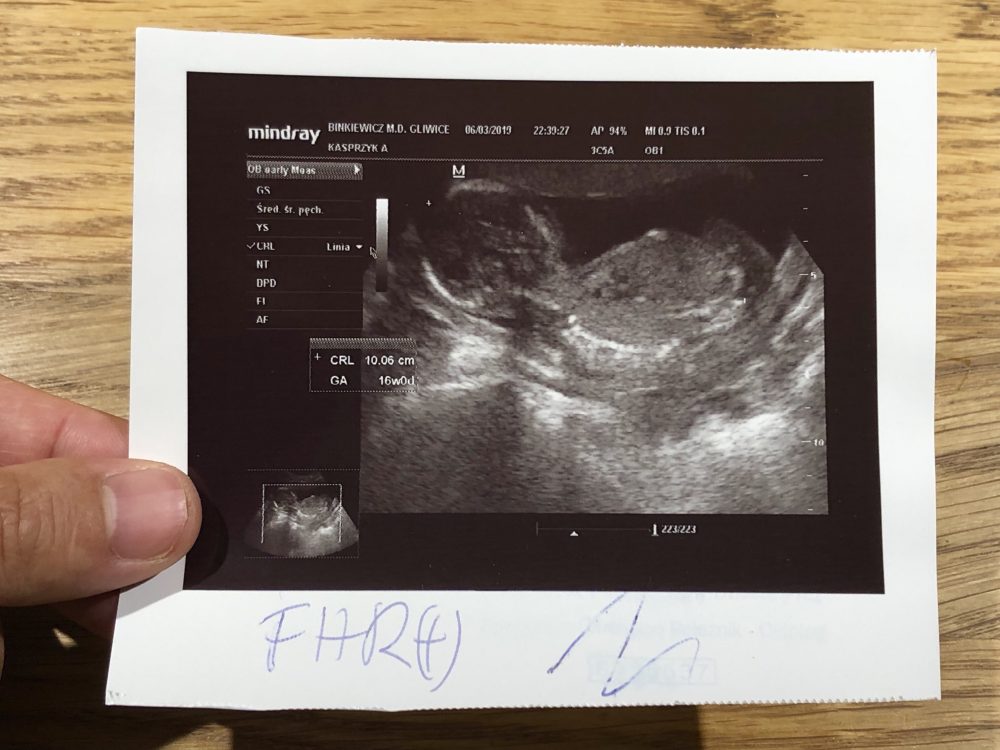

16週の2d画像 男女の性別判断はできますか 妊娠のq A 締切済み Okwave

16週 定期健診とカリフォルニア州のスクリーニングプログラム 血液検査 性別判明 Taekoのocへいこう

妊娠11週1日 11w1d の超音波 エコー 写真

妊娠11週4日 11w4d の超音波 エコー 写真